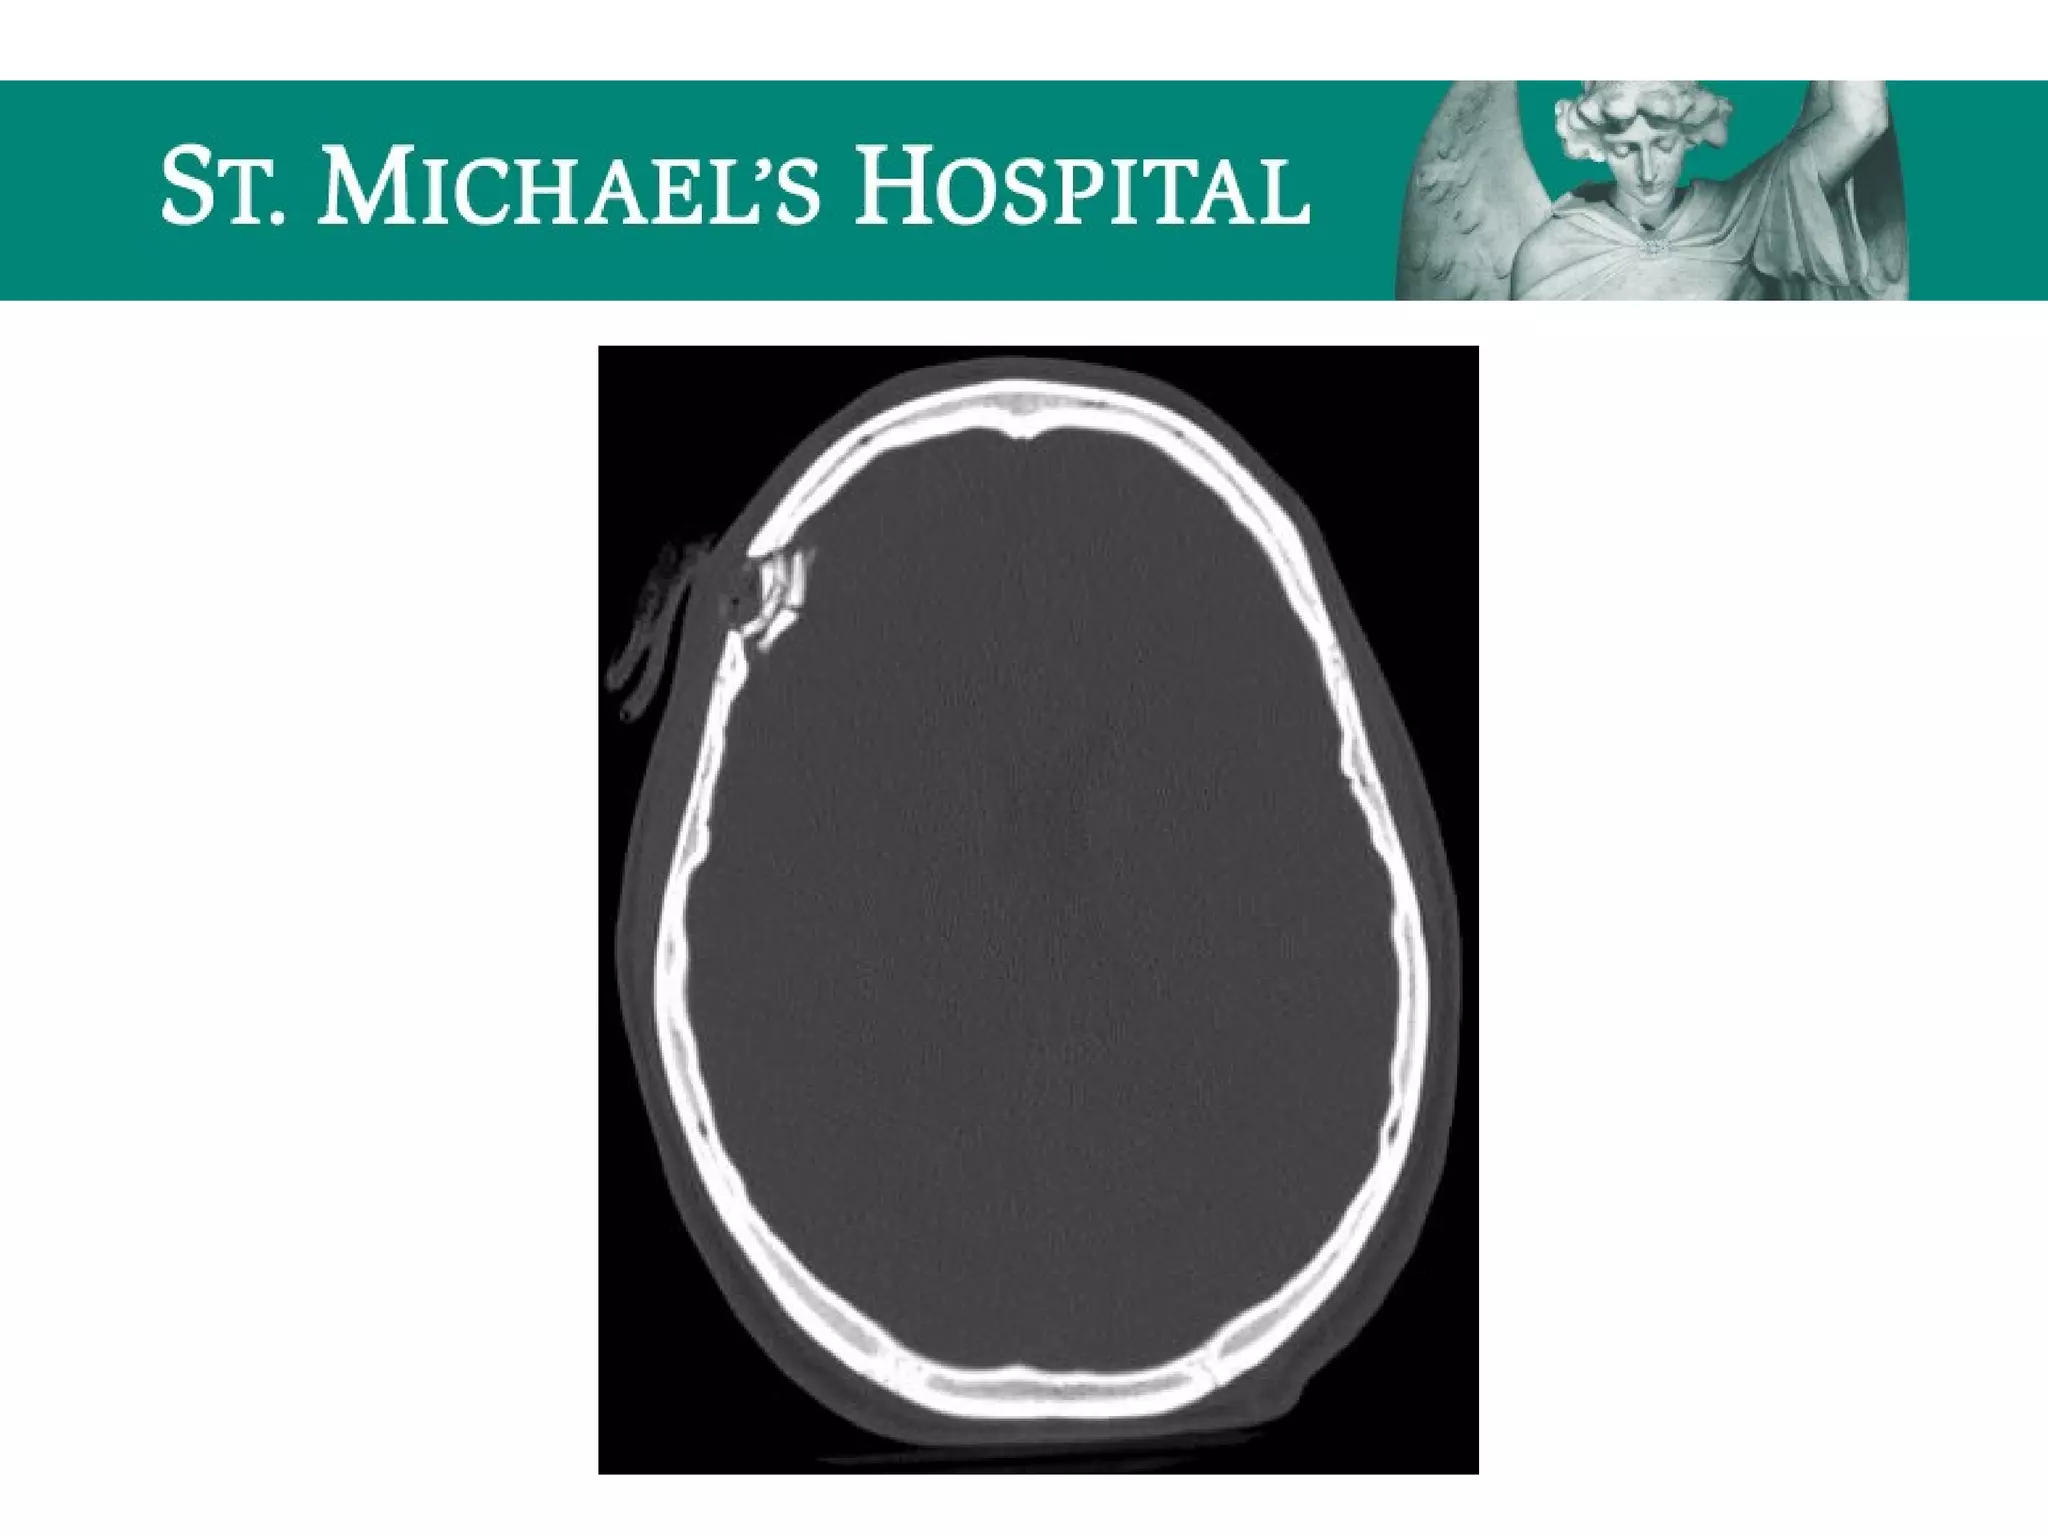

Hydrocephalus

 CSF is produced in the choroid plexus and absorbed into the venous

system via the arachnoid granulations

 Hydrocephalus results from an excess of CSF, due to an imbalance in

CSF production and absorption, resulting in increased intra-ventricular

pressure

 Classification:

 Communicating (non-obstructive)  blockage of CSF flow beyond

the outlet of the 4th

ventricle

 Non-communicating (obstructive)  blockage of CSF flow within

the ventricular system, with dilatation proximal to the obstruction

Communicating Hydrocephalus

 Blockage of CSF flow over the cerebral convexities/absorption at the arachnoid

granulations secondary to:

– SAH, meningeal mets, granulomatous meningitis

 Rapid CSF production

 eg. choroid plexus papilloma

 Radiological features:

 Symmetrical enlargement of the lateral, third and fourth ventricles

 Normal/effaced cerebral sulci

 Dilatation of subarachnoid cisterns

 Periventricular low attenuation  transependymal flow of CSF

Hydrocephalus  CSF isproduced in the choroid plexus and absorbed into the venous system via the arachnoid granulations  Hydrocephalus results from an excess of CSF, due to an imbalance in CSF production and absorption, resulting in increased intra-ventricular pressure  Classification:  Communicating (non-obstructive)  blockage of CSF flow beyond the outlet of the 4th ventricle  Non-communicating (obstructive)  blockage of CSF flow within the ventricular system, with dilatation proximal to the obstruction

Communicating Hydrocephalus  Blockageof CSF flow over the cerebral convexities/absorption at the arachnoid granulations secondary to: – SAH, meningeal mets, granulomatous meningitis  Rapid CSF production  eg. choroid plexus papilloma  Radiological features:  Symmetrical enlargement of the lateral, third and fourth ventricles  Normal/effaced cerebral sulci  Dilatation of subarachnoid cisterns  Periventricular low attenuation  transependymal flow of CSF